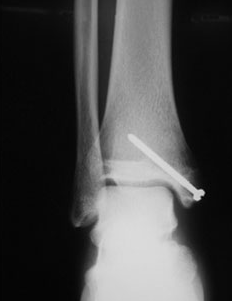

6. 발관절 탈구 골절

오토바이 사고나 운동 등으로 발 관절에 강한 힘이 가해지면 외과와 내과의 골절과 함께 발관절의 외방 탈구가 일어나게 되는데, 이때 발관절은 강하게 변형되어 부어오르게 되며 대부분은 발관절의 인대 손상등을 동반하게 됩니다.

외과와 내과를 플레이트와 강선등으로 고정시키고, 특히 외과의 정확한 정복과 고정이 중요하며 인대가 끊어졌다면 봉합 수술을 병행할 수 있습니다.